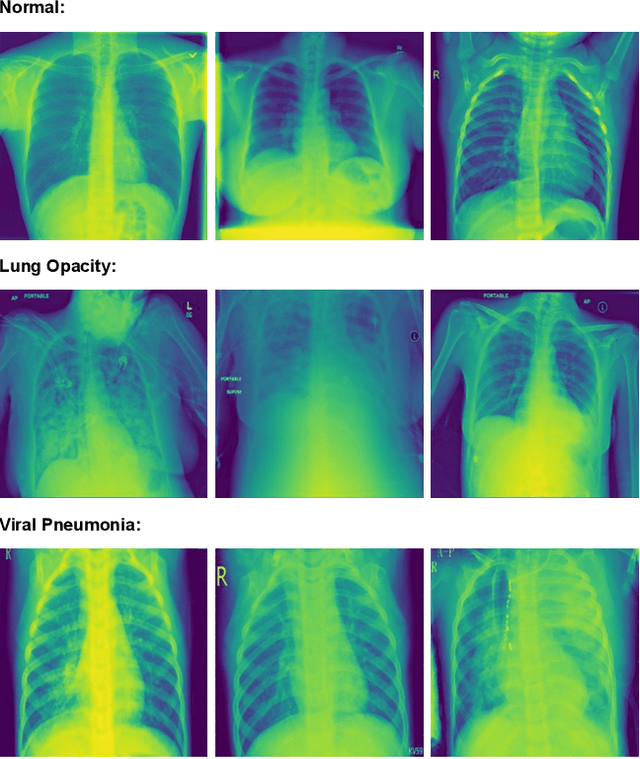

Abstract:Many people die from lung-related diseases every year. X-ray is an effective way to test if one is diagnosed with a lung-related disease or not. This study concentrates on categorizing three distinct types of lung X-rays: those depicting healthy lungs, those showing lung opacities, and those indicative of viral pneumonia. Accurately diagnosing the disease at an early phase is critical. In this paper, five different pre-trained models will be tested on the Lung X-ray Image Dataset. SqueezeNet, VGG11, ResNet18, DenseNet, and MobileNetV2 achieved accuracies of 0.64, 0.85, 0.87, 0.88, and 0.885, respectively. MobileNetV2, as the best-performing pre-trained model, will then be further analyzed as the base model. Eventually, our own model, MobileNet-Lung based on MobileNetV2, with fine-tuning and an additional layer of attention within feature layers, was invented to tackle the lung disease classification task and achieved an accuracy of 0.933. This result is significantly improved compared with all five pre-trained models.